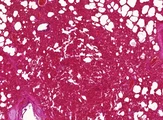

![]() | zawał krwawy płuc | 50%